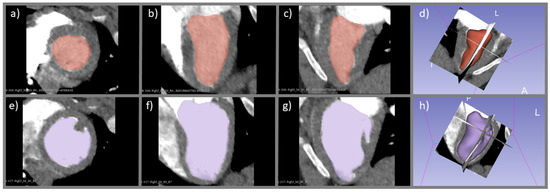

2.5. Derivation of CO Index with Ventricular Delineation Method